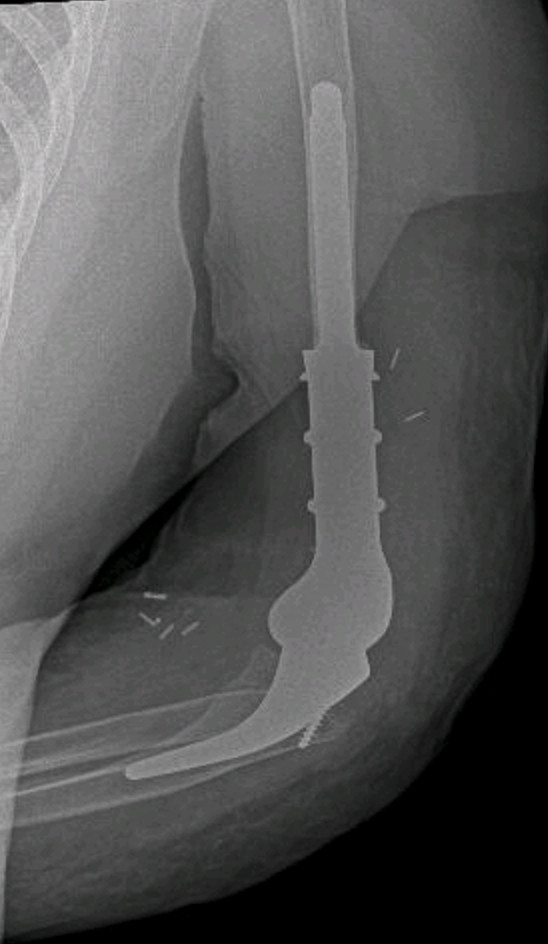

Codo

El codo es una articulación compleja que combina movilidad, fuerza y estabilidad. Cuando se ve afectado, incluso las actividades más sencillas —como vestirse, escribir o practicar deporte— pueden volverse dolorosas o imposibles. En delamanoalcodo tratamos de forma especializada las lesiones y enfermedades del codo, con un enfoque centrado en recuperar la función y reducir el dolor.

Patologia de codo mas comunes

• Fracturas del codo (húmero distal, cabeza radial, olécranon)

• Luxaciones de codo

• Rigidez postraumática del codo

• Artrosis de codo

• Secuelas de traumatismos o cirugías previas